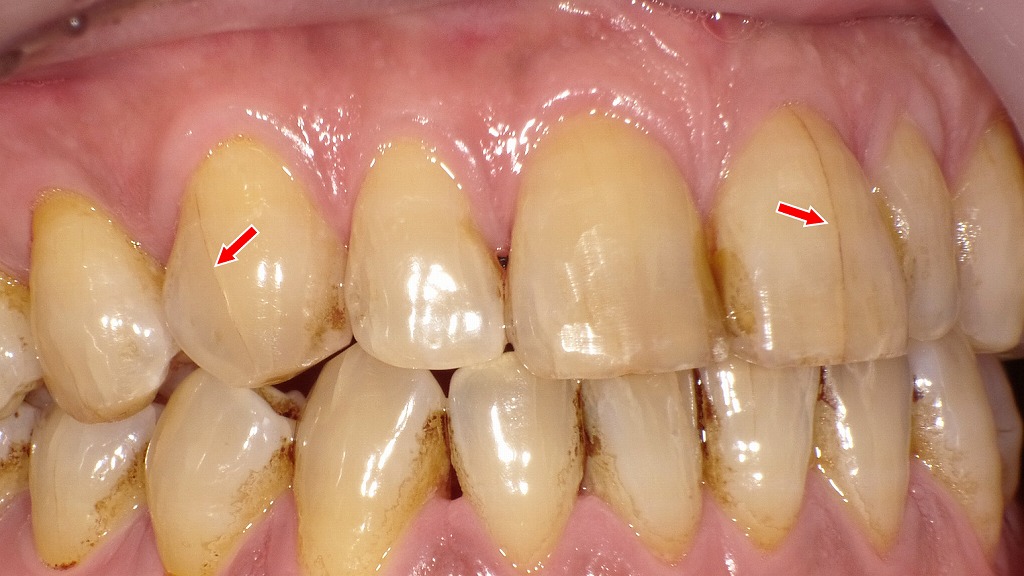

赤い矢印で示されている部分では、歯ぐきが本来の位置よりも下がっており、歯の根元(歯根部)が露出しています。健康な状態では、歯ぐきが歯の根元を覆っていますが、歯肉退縮が進むと、白く硬いエナメル質の下にある象牙質が見えるようになります。

赤矢印で示す部分は、歯の表面に生じた細かなヒビ(クラック)です。歯にヒビが入ると、冷たい飲み物や風が当たった際に刺激が神経へ伝わりやすくなり、「キーン」としみる症状が出ることがあります。見た目では分かりにくく、虫歯がなくても知覚過敏の原因になるため、症状が続く場合は早めの歯科受診が重要です。